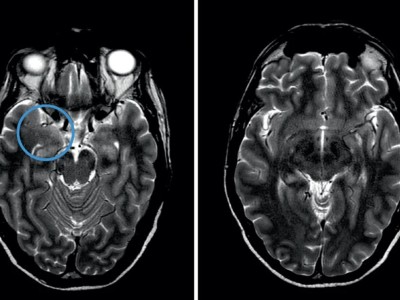

Onkologischer Patient mit Verwirrtheit, Amnesie, Ataxie - Ihre Diagnose?

Jede neuropsychiatrische Symptomatik bei Personen unter Immuncheckpointinhibition verlangt eine umgehende Abklärung. So auch bei diesem 67-jährigen Patienten mit malignem Melanom. Klinisch-neurologisch zeigte er Orientierungslosigkeit, Kurzzeitgedächtnisstörungen, kognitive Verlangsamung, leichte Stand- und Gangataxie sowie einen Tremor.

Untersuchung des Beins eines Patienten/© Visionär / Fotolia, Tinospora cordifolia/© SUBASCHANDRA / Stock.adobe.com, Akute Appendizitis/© Springer Medizin, Älterer Mann im Krankenhausbett hinter Infusionsständer/© Ugurhan Betin / Getty Images / iStock (Symbolbild mit Fotomodell), Ärztin misst Frau den Blutdruck/© New Africa / stock.adobe.com (Symbolbild mit Fotomodellen), Mann appliziert Salbe auf sein Knie/© Ake Ngiamsanguan / Getty Images / iStock (Symbolbild mit Fotomodell), Junger Mann bekommt einen Zugang gelegt/© Tyler Olson / Stock.adobe.com (Symbolbild mit Fotomodell), Colitis ulcerosa/© Springer Medizin Verlag GmbH, Frau hält Tabletten in der Hand/© Liderina / Getty Images / iStock (Symbolbild mit Fotomodell), Älterer Mann schaut kritisch auf Tabletten/© Mediteraneo / stock.adobe.com (Symbolbild mit Fotomodell), EKG-Kontrolle in einer Praxis/© Inside Creative House / Getty Images / iStock (Symbolbild mit Fotomodell), Frau mit schmerzverzerrtem Gesicht in Wohnzimmer/© fizkes / stock.adobe.com (Symbolbild mit Fotomodell), Titel/© CandyRetriever / Stock.adobe.com (Symbolbild mit Fotomodell), Senior liegt im Krankenhaus/© Mat Hayward / Fotolia (Symbolbild mit Fotomodell), Ein alter Mann schaut aus dem Fenster/© Willowpix / Getty Images / istock (Symbolbild mit Fotomodell), Infusion/© pix4U / Stock.adobe.com (Symbolbild mit Fotomodell), Pillenbox mit Tabletten für jeden Wochentag/© von Lieres / Fotolia, Ältere Frau mit Beipackzettel und Pillen/© Ridofranz / Getty Images / iStock (Symbolbild mit Fotomodell), Tabletten zur Krebstherapie/© RFBSIP / stock.adobe.com (Symbolbild mit Fotomodell), Mann wird im Krankenwagen notfallmäßig versorgt/© Kzenon / Stock.adobe.com (Symbolbild mit Fotomodell), Arzt misst Blutzucker per Glucometer/© geargodz / Stock.adobe.com (Symbolbild mit Fotomodell), cMRT-T2w-Sequenzen: hippocampale Ödeme/© Schütz. F. / all rights reserved Springer Medizin Verlag GmbH, Schmerzende livide Areale am Bauch/© A. Frahnert, Messen des Bauchumfangs/© Halfpoint / stock.adobe.com (Symbolbild mit Fotomodell), Infusionen/© sudok1 / stock.adobe.com, Search Icon, Ärztin mit Nierenhologramm/© Ascendis Pharma, Zwei Sonnenschirme vor blauem Hintergrund/© MicroStockHub | iStock, Paar spaziert am Strand/© kate_sept2004 | iStock (Symbolbild mit Fotomodellen), Schematische Darstellung der Schilddrüse/© Dr_Microbe | iStock